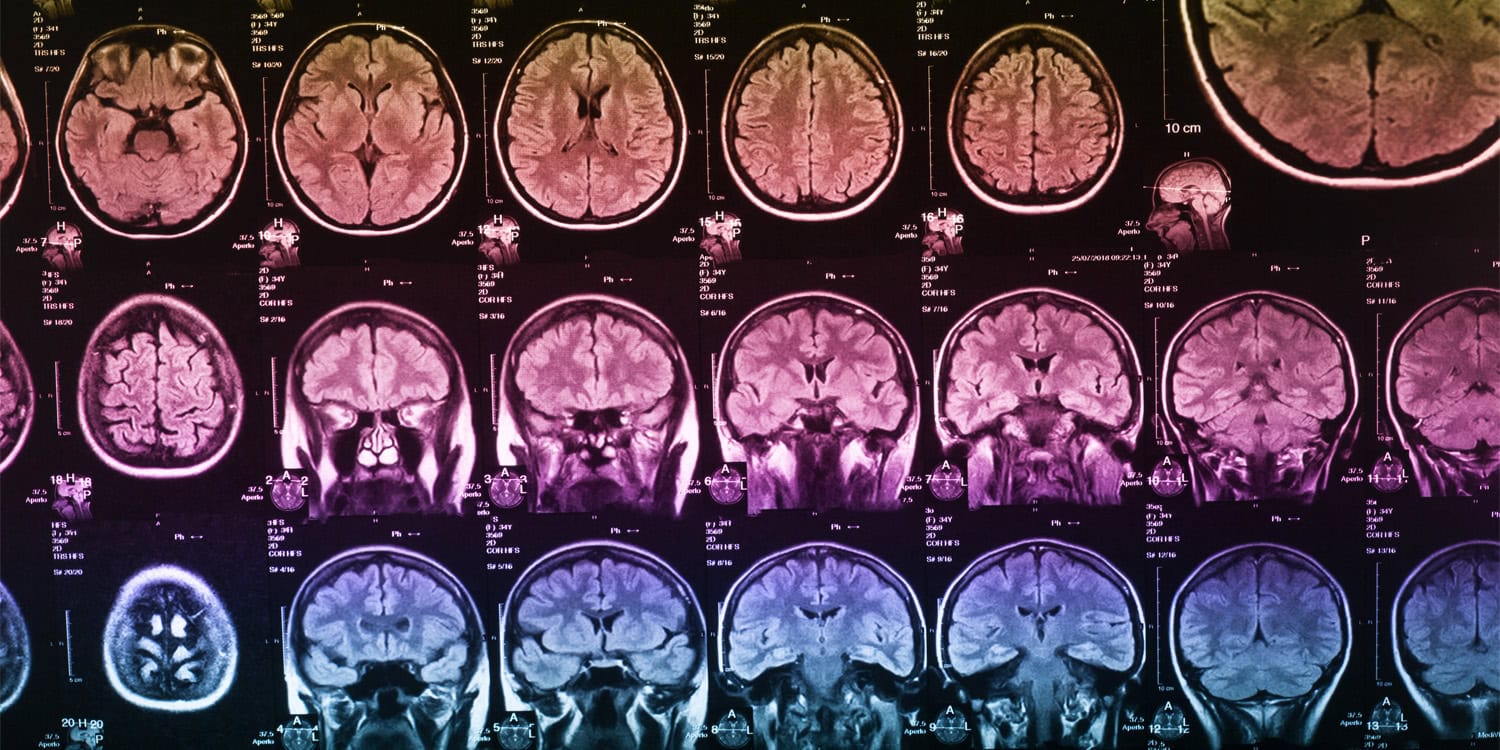

Большинство прошлых исследований изучали эту головоломку сканированием мозга с помощью fMRI — технология хорошая, но следит только за кровотоком в разных областях мозга. Чтобы увидеть танец отдельных молекул, нужна гораздо тоньше аппаратура — так называемый ПЭТ-сканер, способный "подсмотреть", какие именно рецепторы заняты и чем.

После ПЭТ-марафона на очереди был ещё и МРТ — теперь уже привычный способ смотреть на изменения кровотока, чтобы увидеть, какие зоны загораются при звуках любимых треков. Ожидаемо — активизировались не только эмоциональные центры, но и области, отвечающие за восприятие собственного тела (insula и передняя поясная кора).